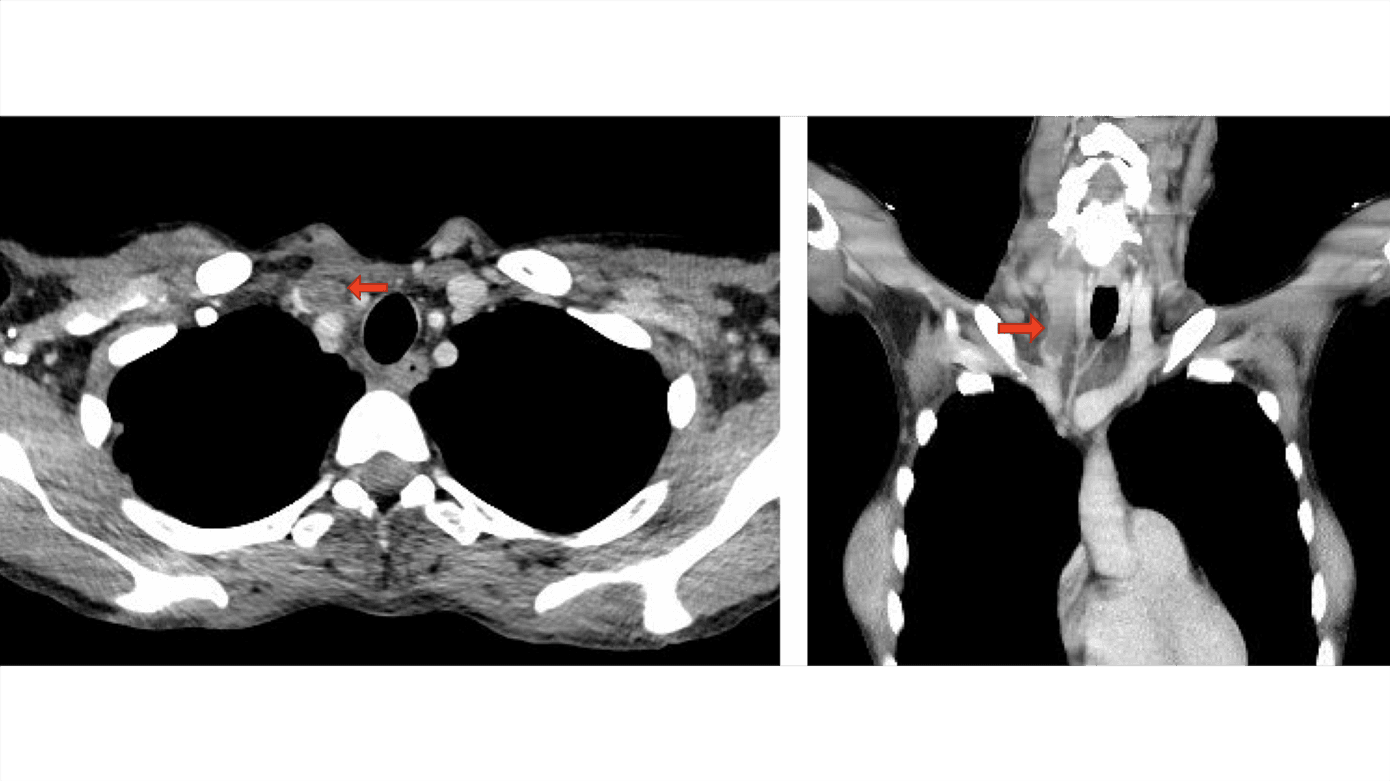

En 48-årig kvinde blev indlagt med kraftige halssmerter, diffus ømhed i nedre del af abdomen samt tiltagende svækkelse og påvirket almentilstand. Objektive fund var højrøde slimhinder i mundhulen og en 6 × 4 cm fast, øm udfyldning på højre side af halsen ved nederste tredjedel af m. sternocleidomastoideus. Patienten var febril (38,5 °C) med forhøjede infektionstal, leukocytter 14,1 × 109/l og et C-reaktivt proteinniveau på 93 mg/l. På formodning om bakteriel infektion blev der påbegyndt behandling med piperacillin/tazobactam. Bloddyrkning taget efter opstart af antibiotikabehandlingen var uden vækst af bakterier. På mistanke om LS blev der udført en CT af hals og thorax. CT’en viste en større trombe i VJI dexter (Figur 1), hvorfor det samlede sygdomsbillede var foreneligt med LS.